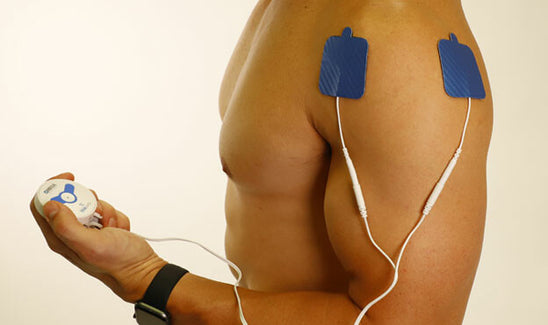

TENS stands for (Transcutaneous Electrical Nerve Stimulation). TENS therapy units are predominately used for nerve related pain conditions (acute and chronic conditions). TENS machines work by sending stimulating pulses across the surface of the skin and along the nerve strands.

The stimulating pulses help prevent pain signals from reaching the brain. TENS devices also help stimulate your body to produce higher levels of its own natural painkillers, called "Endorphins".

E.M.S. stands for (Electrical Muscle Stimulation) which are predominately used to prevent, or reduce, muscle atrophy. Atrophy is the weakening and loss of muscle tone, which is usually experienced after surgeries or injuries. EMS has been proven to be an effective means of preventing muscle atrophy. EMS also helps by increasing blood flow to muscles, increasing range of motion, increasing muscle strength, as well as enhancing muscle endurance. Muscle Stimulators have pain management attributes in helping muscle related pain, such as a spastic muscle, sore muscles, or tight muscles.

If you're seeking relief from chronic pain or looking to accelerate muscle recovery, TENS therapy and EMS devices offer proven solutions. By delivering gentle electrical impulses, these devices help manage discomfort, improve circulation, and enhance muscle strength. Whether you're recovering from an injury, dealing with persistent neck or back pain, or simply aiming to improve your overall wellness, TENS and EMS can support your journey toward better health. Explore our range of devices designed to meet various therapeutic needs and experience the benefits of targeted, effective treatment.